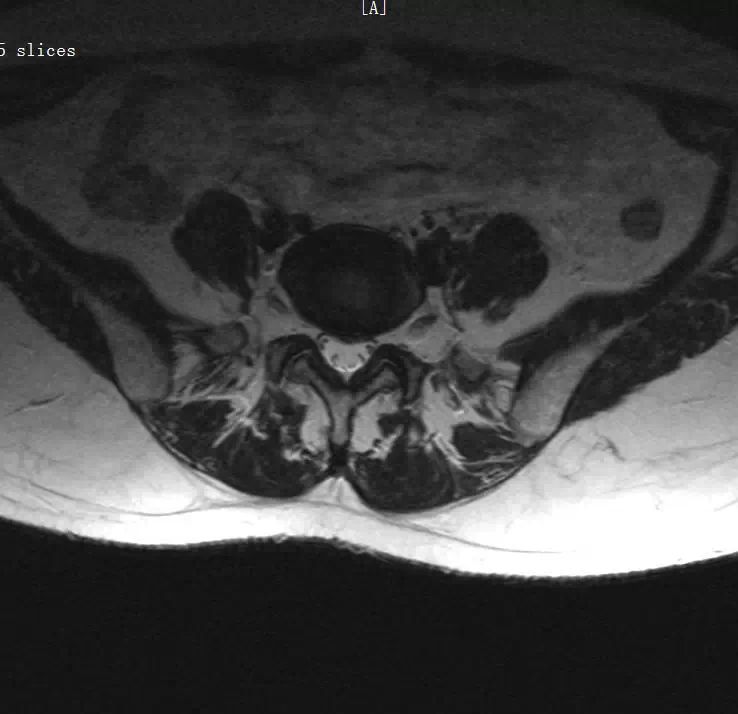

1、腰椎间盘突出症(L4/S1)。

患者腰部生理弧度可,腰部活动度可,腰背部肌张力略高,L4—S1棘间以及椎旁压叩痛(+),以L4—S1左侧为甚,双侧臀上皮神经压痛(+),挺腹试验(-),双直腿抬高试验:(-),加强征(-),梨状肌紧张试验(-),阔筋膜张肌紧张松弛试验(-),双下肢皮肤浅感觉正常,双下肢未见肿胀,双下肢肌力Ⅴ级,膝、跟腱反射(++),巴彬氏征(-)。

西医诊断:1、腰椎间盘突出症(L4/S1) 2、腰椎退行性骨关节病 3、骶尾部筋膜炎 4、腰椎椎间孔镜术后